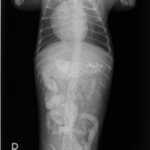

症例:炎症性ポリープ M.ダックス 10歳 オス

主訴:8ヶ月前から便が細くなり、血が混じることがある。その他、元気・食欲等、一般状態は良好。

経過:超音波検査にて直腸壁の肥厚(5㎜)が認められた。また、直腸検査で直腸全周に結節状病変を触知し、出血も確認された。消炎剤、抗生剤、整腸剤による治療への反応が長期的に悪いため、生検も含めた内視鏡検査を実施した。

内視鏡検査:肛門付近の直腸全周に、炎症および出血を伴う結節状病変を多数認めた。

病理検査:直腸の病変は、良性の非腫瘍性病変の一つである“炎症性ポリープ”と診断された。

診断後経過:炎症性ポリープは多発する傾向や腫瘍に転化する可能性があるため、消炎剤、抗生剤、整腸剤による内科療法を継続しながら、現在プルスルー法による外科的摘出術を検討中。

◎炎症性ポリープとは

近年、ミニチュアダックスで好発が知られている良性の腫瘍性の病変です。しばしば多発し、また腫瘍に転化する事があります。